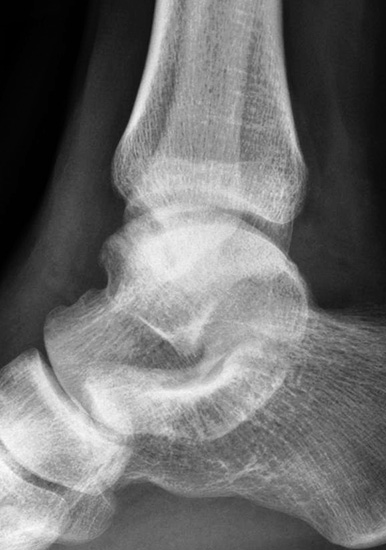

- Röntgenaufnahme des OSG in 2 Ebenen (seitlich und Mortiseview).

- MRT des OSG zur Beurteilung des ligamentären Schadens und möglicher Knorpelläsionen.

- Ggf. CT zur Bestimmung der Lage und Größe begleitender Osteophyten oder freier Gelenkkörper, sofern diese als Begleitpathologien vorliegen.

- Klinische Untersuchung und Dokumentation des Talusvorschubs, des lateralen und des medialen Tilts sowie der Rotationsinstabilität.